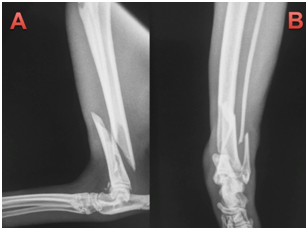

This paper reports the use of a combination of cerclage wire and a neutralization plate in two cats, resulting in primary bone healing. Two non-pedigree male cats (cat 1 and 2), cat 1 weighing 4.1kg and cat 2 weighing 3.9kg, were presented at the Veterinary Hospital of the Federal Univer- sity of Paraná following automobile trauma. General physical examination was unremarkable apart form orthopedic abnormalities. On orthopedic examination, instability, pain and crepitatus were found in the distal region of left tibia and fibula, indicative of fracture. Ventrodorsal and right lateral thoracic radiographs (to rule out pulmonary contusion) were made as well as craniocaudal and lateral views of the tibial and left fibula processes. One cat was presented with a closed tibial fracture. Pre-operative radiographs showed long oblique fractures of the distal third of the tibial diaphysis. The radiographs of the affected limbs of animals 1 and 2, are (Figure 1) (Figure 2), respectively.

Figure 2 Cat 2, with diagnosis of oblique fracture in the distal region of the left tibia and transverse fracture in the left distal fibula.

1. Lateral-medial projection with oblique fracture in the left distal tibia.

2. Craniocaudal projection showing oblique fracture in the distal tibia.